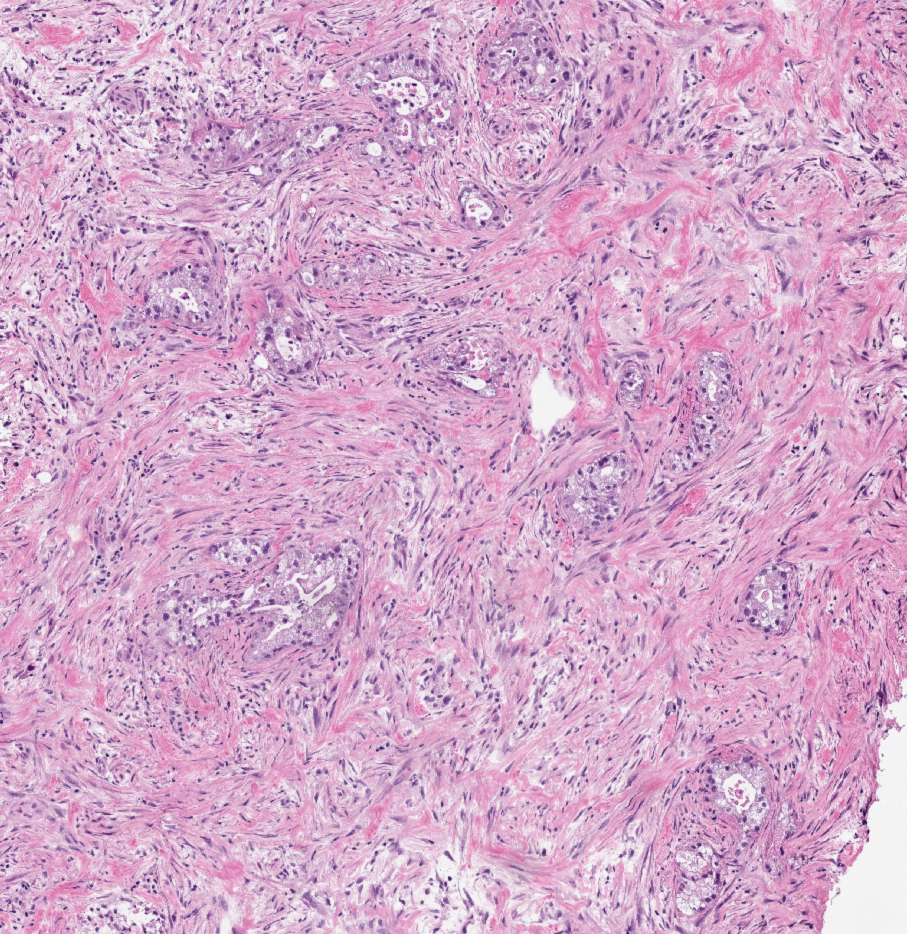

Transcription phenotypes of pancreatic cancer are driven by genomic events during tumour evolution

Authors: Michelle Chan-Seng-Yue, Jaeseung C. Kim, Gavin W. Wilson, Karen Ng, Eugenia Flores Figueroa, Grainne M. O’Kane, Ashton A. Connor, Robert E. Denroche, Robert C. Grant, Jessica McLeod, Julie M. Wilson, Gun Ho Jang, Amy Zhang, Anna Dodd, Sheng-Ben Liang, Ayelet Borgida, Dianne Chadwick, Sangeetha Kalimuthu, Ilinca Lungu, John M. S. Bartlett, Paul M. Krzyzanowski, Vandana Sandhu, Hervé Tiriac, Fieke E. M. Froeling, Joanna M. Karasinska, James T. Topham, Daniel J. Renouf, David F. Schaeffer, Steven J. M. Jones, Marco A. Marra, Janessa Laskin, Runjan Chetty, Lincoln D. Stein, George Zogopoulos, Benjamin Haibe-Kains, Peter J. Campbell, David A. Tuveson, Jennifer J. Knox, Sandra E. Fischer, Steven Gallinger & Faiyaz Notta.

Reference: Nature

DOI: 10.1038/s41588-019-0566-9

Year: 2020